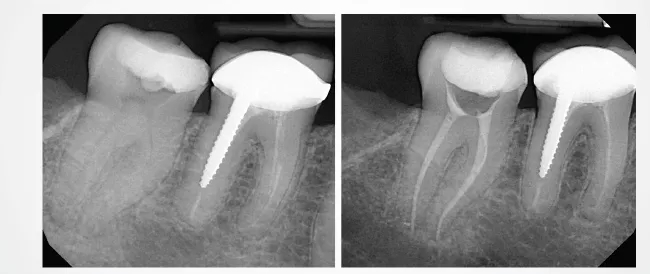

When the canals were obturated to the corresponding Pro-Taper Gold files, the matching gutta-percha typically fit well and went to working length, with the exception of three canals where the gutta-percha extruded well out of the apex, even in situations where the file did not nor could not pass out the apex. In those situations, the gutta-percha was trimmed to fit the working length. Radiographic examination of the teeth revealed three other canals where the gutta-percha was short approximately 0.5-1mm.

Obturation with the fitted gutta-percha went to working length and fit the canals well in most cases; however, the gutta-percha extended out the apex in one canal because of a larger anatomical foramen, and the gutta-percha stopped short in six other canals. Three of those canals had ledging caused by the X1 and X2 files and patency could not be regained, so the gutta-percha could not reach the full working length. And, in one instance, the gutta-percha stopped short, but upon re-instrumentation of the canal three more times, the gutta-percha was able to be seated to the full working length.

The Medium Fine (MF) 0.04 taper Kerr AutoFit Greater Taper gutta-percha was used with the 0.04 taper ZenFlex files, and had to be trimmed to the corresponding master apical file size. Once fitted and trimmed, there were no issues seating the gutta-percha to the established working length. Should a clinician use the 0.06 taper ZenFlex files, the AutoFit Greater Taper gutta-percha is also available in a 0.06 taper to match.

Two dimensional radiographs were taken of the teeth after endodontic therapy was completed and reviewed. In some of the ProTaper Gold and Next cases, working length was not reached radiographically, even though it was thought to be achieved clinically. As an electronic apex locator cannot be used to assess working length on extracted teeth, working length was established with visual observation. Clinically, an electronic apex locator would have been used, and adjustments would have been made throughout the entire process to ensure the working length was reached. The teeth were selected at random, and some of the orifices and canals were calcified or stenotic. In a live clinical scenario, ultrasonics would have been used to negotiate these constrictions more easily; however that being said, the ZenFlex and Traverse file systems allowed these canals to be negotiated and treated without issue. Additionally, the teeth treated with the ZenFlex files appeared to have the best preservation of the natural shape of the canal and conserved the most tooth structure. This was not the case with the ProTaper Gold and Next file systems. Less efficient cutting with more aggressive removal of tooth structure was noted, resulting in a loss in the original anatomy of the canals. ZenFlex is an ideal file that balances strength and flexibility to allow clinicians to reach the working length while being minimally invasive, even in cases with complex canal anatomies.